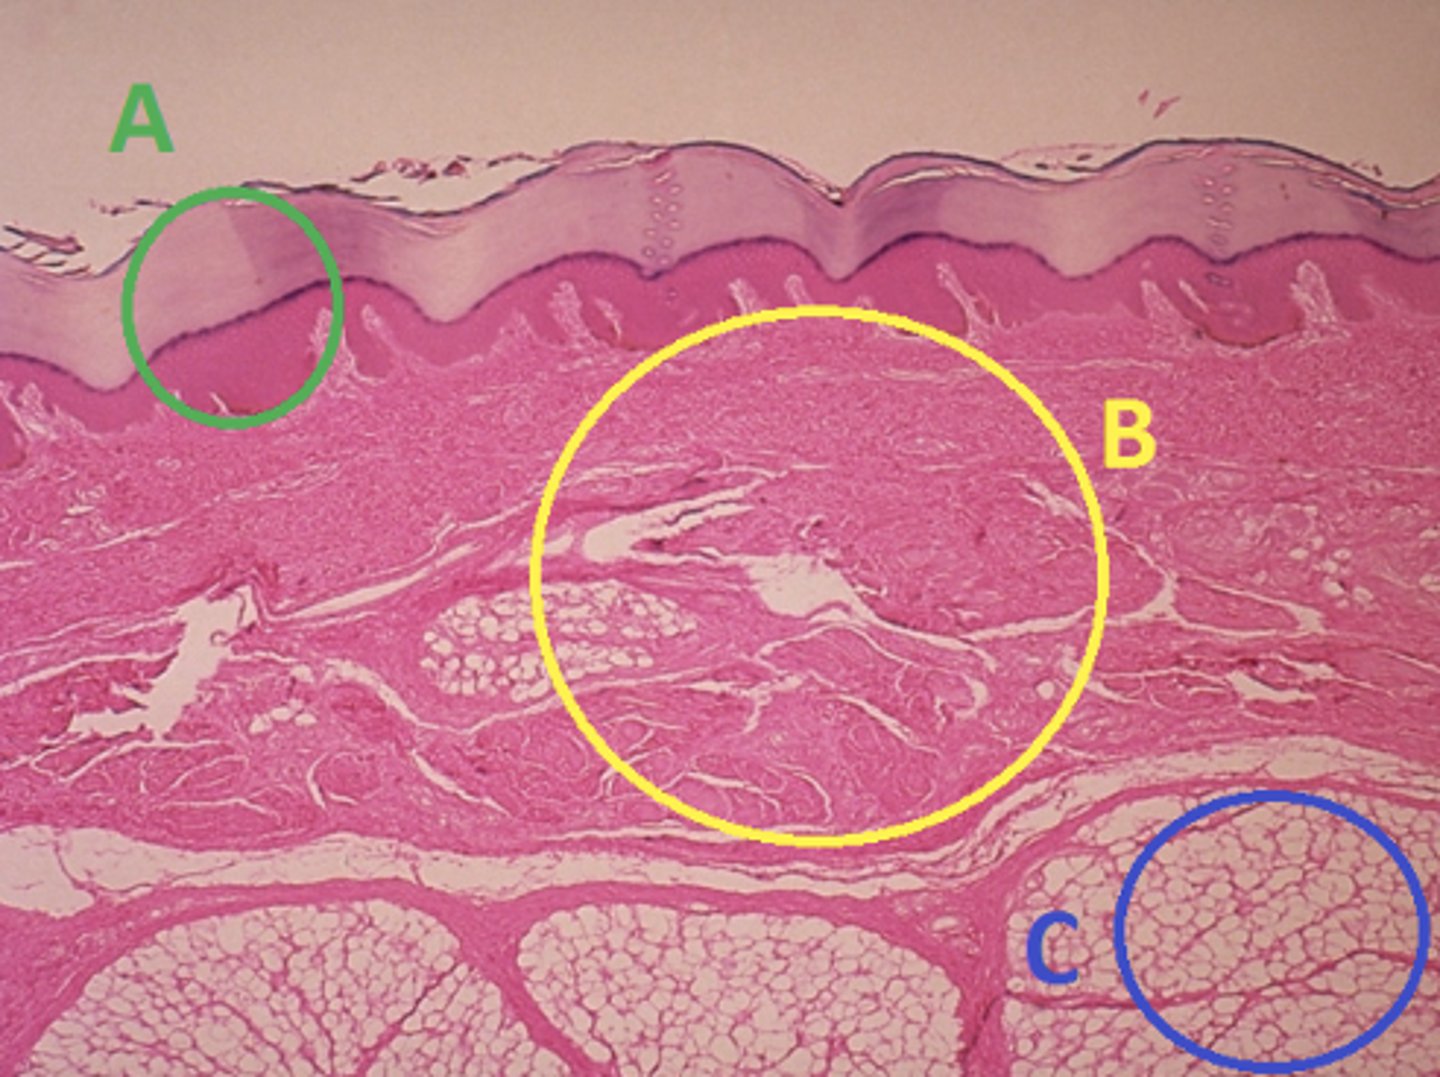

C - hypodermis

Answer the following questions based on the features indicated in the following image. Which letter indicates the administration site for subcutaneous injections?

A - epidermis

Answer the following questions based on the features indicated in the following image. Which letter indicates the administration site for topical creams and ointments?

B - Dermis

Answer the following questions based on the features indicated in the following image. Which letter indicates the administration site for the tuberculin skin test?

A - epidermis

Answer the following questions based on the features indicated in the following image. Which letter indicates a region of the skin with no nerves or blood vessels?

B - Dermis

Answer the following questions based on the features indicated in the following image. Which letter indicates the region where skin appendages (sweat glands, sebaceous glands, and hair follicles) have their roots?

Epithelial tissue

Answer the following questions based on the features indicated in the following image. Which of the four major tissue types is indicated by letter A?

Which letter indicates the administration site for insulin injections?

A

Which letter indicates the administration site for a lidocaine patch?

B

Which letter indicates the administration site for an allergy test?

B

Which letter indicates a region of the skin rich in dense, irregular connective tissue?

C

Which letter indicates the region most important for energy storage and thermal insulation?

Connective

Which of the four major tissue types is indicated by letter C?

Skin of the dorsal surface (back) of the hand

Which part of the body could the previous image represent?

Skin of the ventral surface (palm) of the hand

Skin of the dorsal surface (back) of the hand